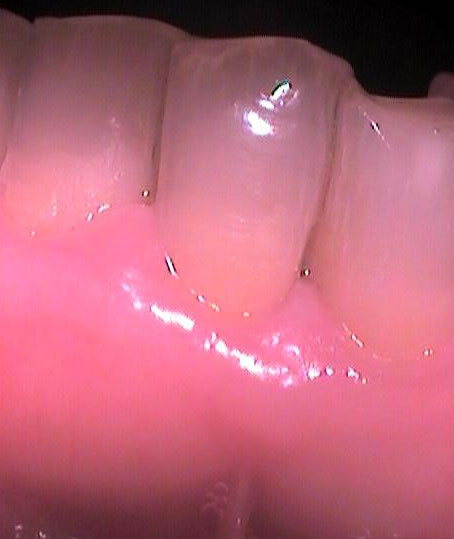

Втори случай

Преди почистване на зъбния камък